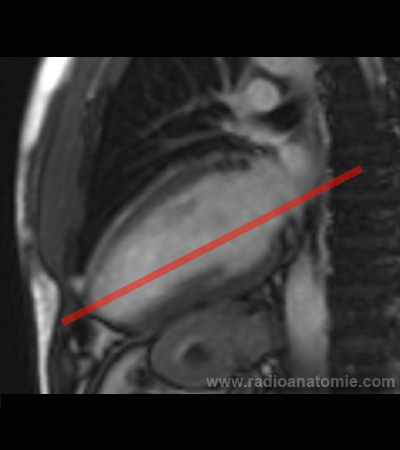

Radioanatomie et plans de coupe en IRM cardiaque

Coupe long axe 2 cavités